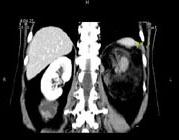

问题 女,64岁,左侧腰部胀痛,行CT扫描,下列说法正确的是 ( )

选项 A、考虑为左侧肾上腺来源的髓样脂肪瘤 B、考虑为腹膜后来源的脂肪肉瘤 C、该病灶密度不均匀,其内可见脂肪密度影,且呈不均匀强化 D、考虑为左肾来源的血管平滑肌脂肪瘤 E、左肾区可见一巨大的占位性病灶,境界较清楚,胰腺尾部受压向前推移

答案 CDE